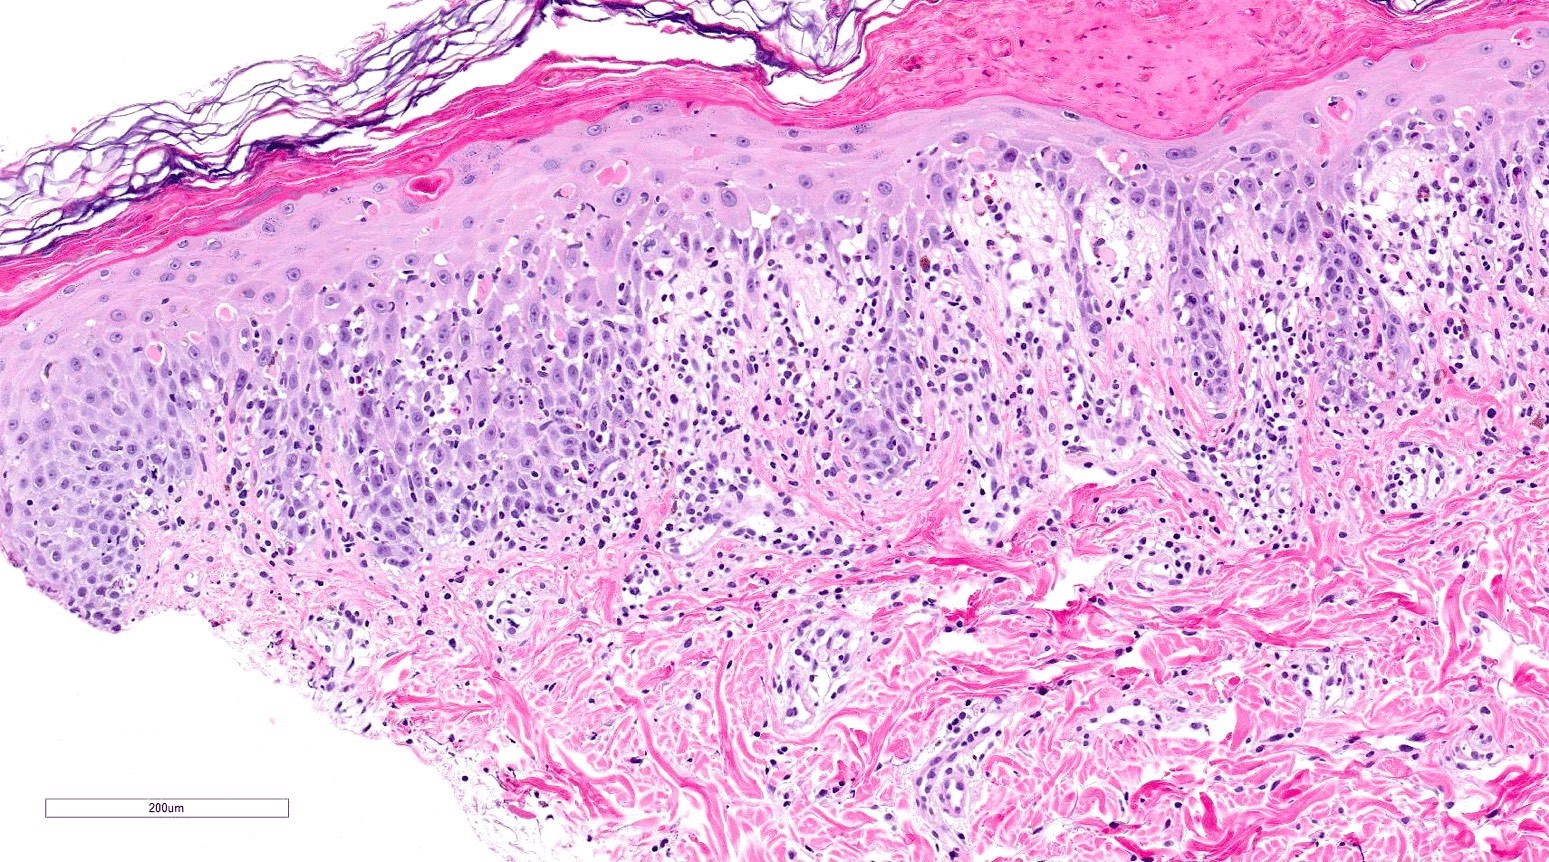

- Acute GVHD (Patterson: Weedon's Skin Pathology, 4th Edition, 2015)

- Mild to moderate superficial perivascular lymphocytic infiltrate with exocytosis of inflammatory cells into the epidermis and basal vacuolation, interface dermatitis

- Scattered, shrunken, eosinophilic keratinocytes with pyknotic nuclei, at all levels of the epidermis; often accompanied by 2 or more lymphocytes, producing the satellite cell necrosis - lymphocyte associated apoptosis

- Occasionally, rare eosinophils can be present; melanin incontinence is prominent in patients with darker skin types

- If severe, subepidermal microvesicles, subepidermal blisters and epidermal necrosis

- Lymphocytic infiltrate in GVHD after solid organ transplantation is usually brisk in comparison to the sparser inflammation following bone marrow transplantation

- Chronic GVHD (Biol Blood Marrow Transplant 2015;21:589, Patterson: Weedon's Skin Pathology, 4th Edition, 2015)

- Chronic lichenoid GVHD

- Acanthosis, orthohyperkeratosis, parakeratosis with hypergranulosis

- Underlying band-like lymphocytic infiltrate with basal layer vacuolization and apoptotic keratinocytes

- Periadnexal inflammation can be present

- May be difficult to distinguish from lichen planus without clinicopathologic correlation; satellite cell necrosis is the most helpful clue in GVHD biopsies to distinguish it from lichen planus

Microscopic (histologic) images

Contributed by Silvija P. Gottesman, M.D. and Ohoud Aljarbou, M.D.